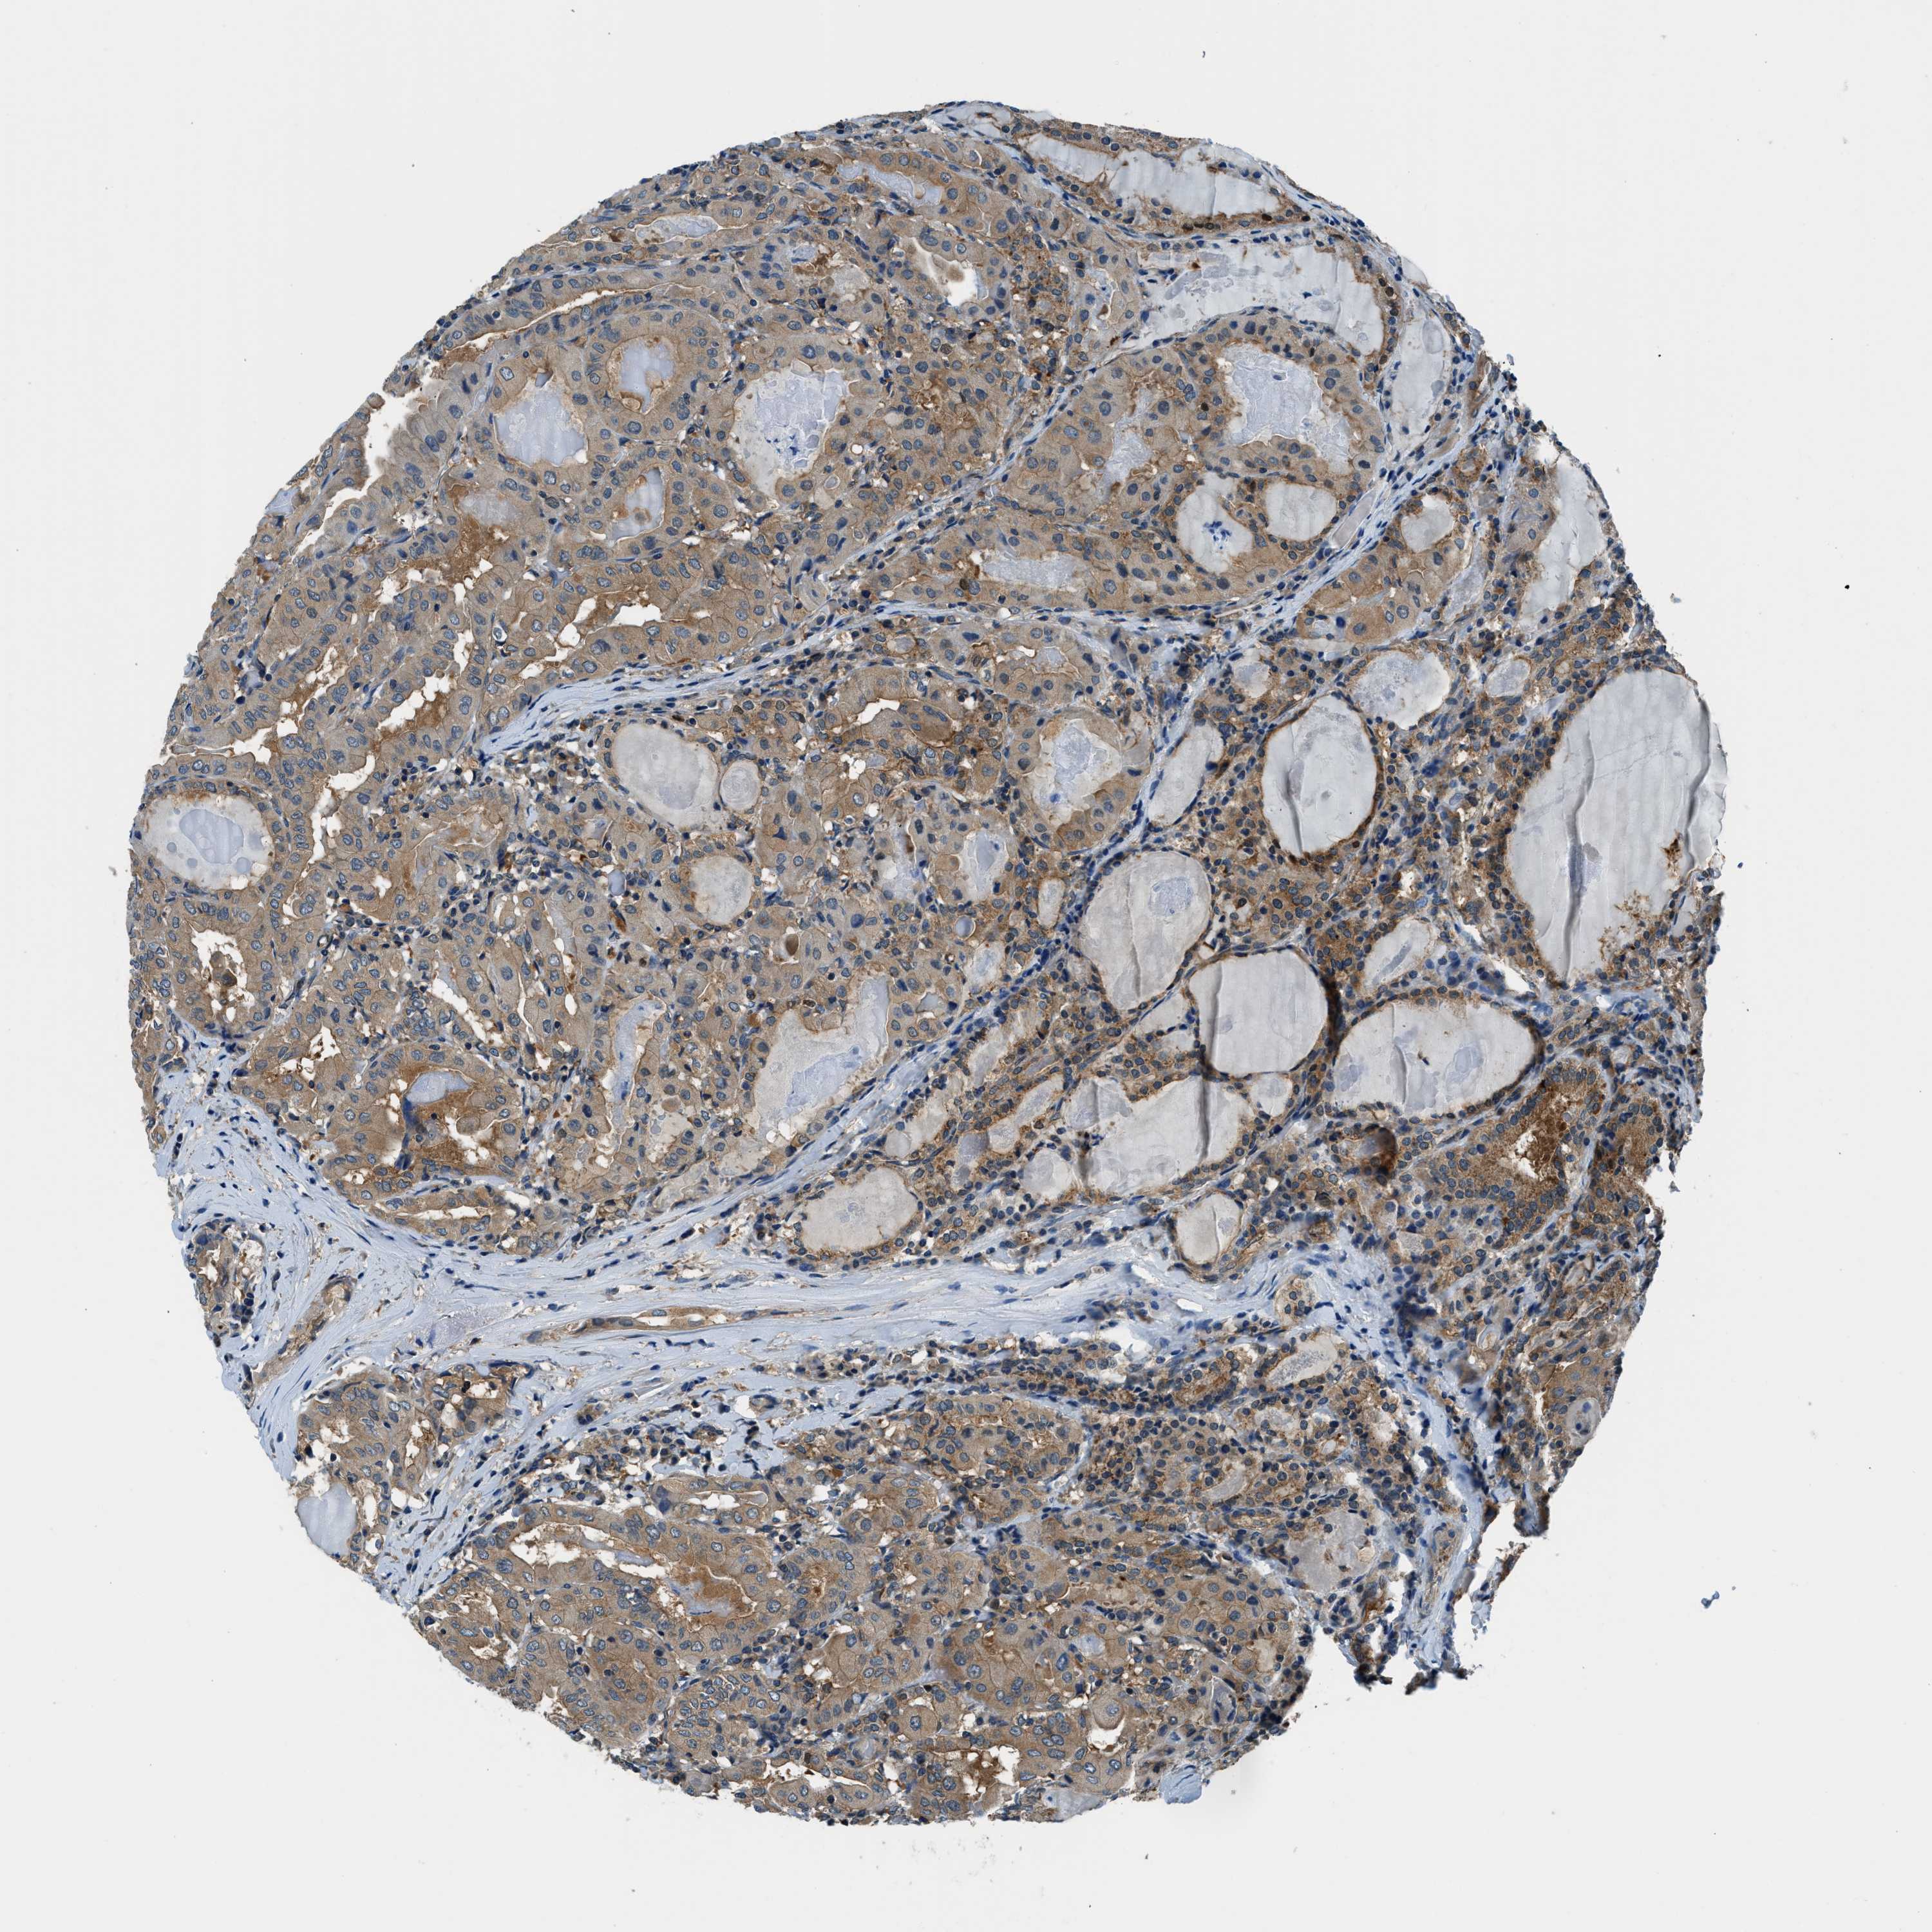

THYROID CANCER - Protein expressioni

A mouse-over function shows sample information and annotation data. Click on an image to view it in a full screen mode. Samples can be filtered based on level of antibody staining by selecting one or several of the following categories: high, medium, low and not detected. The assay and annotation is described here.

Note that samples used for immunohistochemistry by the Human Protein Atlas do not correspond to samples in the TCGA dataset.

Antibody stainingi

Antibody staining in the annotated cell types in the current human tissue is reported as not detected, low, medium, or high, based on conventional immunohistochemistry profiling in selected tissues. This score is based on the combination of the staining intensity and fraction of stained cells.

Each image is clickable and will lead to virtual microscopy that enables deeper exploration of all samples and also displays staining intensity scores, fraction scores and subcellular localization as well as patient and tissue information for each sample.

Antibody HPA006119

Antibody HPA016599

Staining

High

Medium

Low

Not detected

Intensity

Strong

Moderate

Weak

Negative

Quantity

>75%

75%-25%

<25%

None

Location

Nuclear

Cytoplasmic/membranous

Cytoplasmic/membranous,nuclear

Follicular adenoma carcinoma, NOS

Papillary adenocarcinoma, NOS